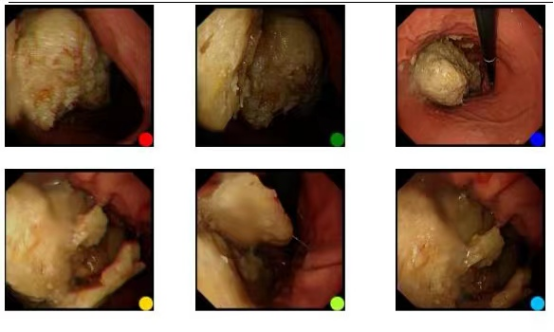

近日,小王(化名)进食一碗山楂2小时后,开始出现腹痛伴呕吐的症状,腹痛剧烈时伴胸痛及呼吸困难,疼痛持续数小时。次日晨起就诊于UG环球国际附属第二医院内科门诊,胃镜检查显示胃部巨大结石(大小约6×7cm),慢性浅表性胃炎。考虑诊断为胃石合并慢性胃炎,给予药物治疗,患者腹痛有所好转。但3天后,仍不能痊愈,经与患者沟通,同意安排胃镜下胃结石碎石治疗术。在全麻辅助下,经胃镜插入钢丝圈套器,分10余次碎石,胃石被分割成数小块。治疗后,未再出现腹痛不适。出院前再次复查胃镜,显示6x7cm巨大结石已全部安全排出。

胃石是一种较常见的上消化道疾病,近年来有逐渐上升的趋势,以往多采用外科手术取石,患者承受痛苦较大,不易接受。但随着内镜的普及和发展,胃石的各种内镜下治疗均取得良好的效果。